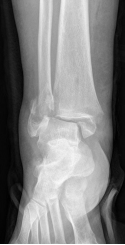

骨折及撕脱骨折

虽然出现相对较少,但是往往和韧带损伤不易区分,最常出现的是腓骨下端骨折和第五跖骨基底骨折。损伤后如果出现剧烈疼痛、肿胀、充血、无法负重等情况,最好要及时就诊,排除骨折的可能。

对于撕脱骨折、韧带断裂等损伤,大多需要拍片明确损伤大小,多数需要手术治疗。而对于软骨损伤、韧带非全层损伤、肌腱损伤、肌肉拉伤等,通过针灸、理疗、正骨等保守治疗,都会取得良好的疗效。